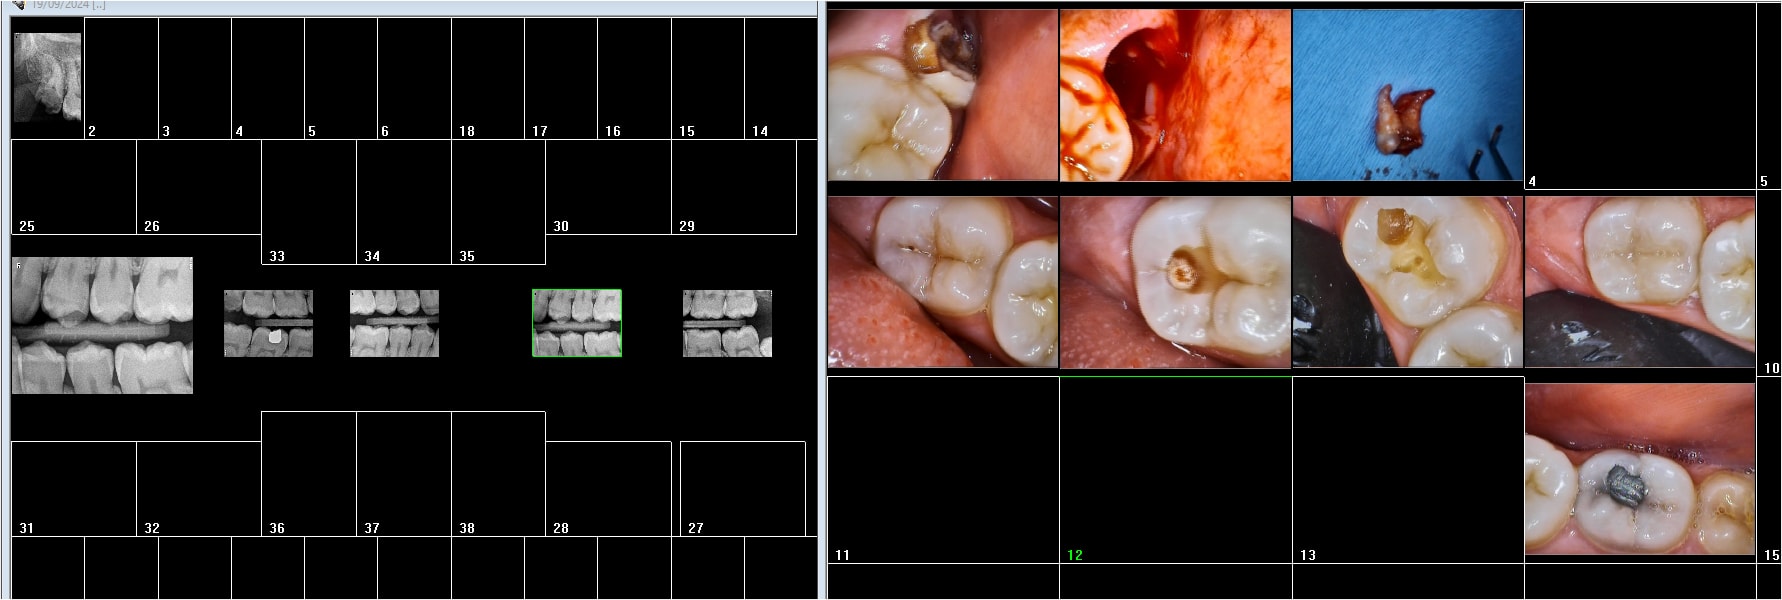

Supprime vite ce vilain trait noir sur la crête marginale distale avec ton blanco, tu mettras tes lunettes la prochaine fois.

C’est peut-être juste une illusion, la faute à polaroid.

Heu dentarue , je vois bien ce trait noir , mais tout ce qui est noir n'est pas une carie ou une fracture .... tu apprendras ça ..ou pas . Mais quand on veut être mauvais , on y arrive facilement .